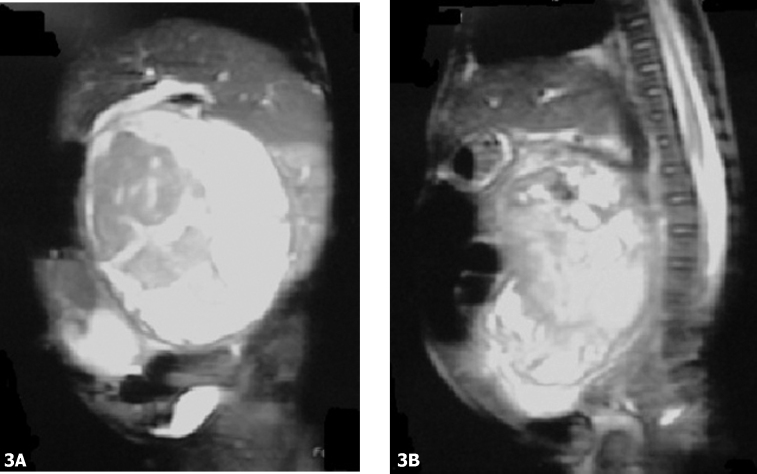

Figure 3.

6-month-old child with pancreatoblastoma. A, Coronal and B, sagittal (b) T2-weighted MR demonstrates a large heterogeneous mass with high signal intensity areas consistent with cystic necrosis and isointense areas compared to the spleen that represents the solid component of the tumor. Cephalad and lateral displacement of the liver and spleen respectively is shown.